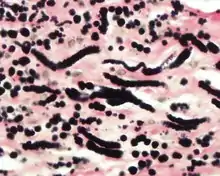

By microscopie view, there is an admixture of heavy dense bands of collagenous tissue dissected by fat and abnormal elastic fibers. The elastic fibers are often quite large and are easily identified. The elastic fibers are coarse, thick, and darkly eosinophilic, often fragmented into globules, creating a "string of pearls" or "pipe cleaner" appearance. Because of degeneration, the elastic fibers will appear as globules with a serrated or "prickled" edge.[5]

The elastic fibers will be highlighted by a Weigert or von Gieson elastic stains.[9]